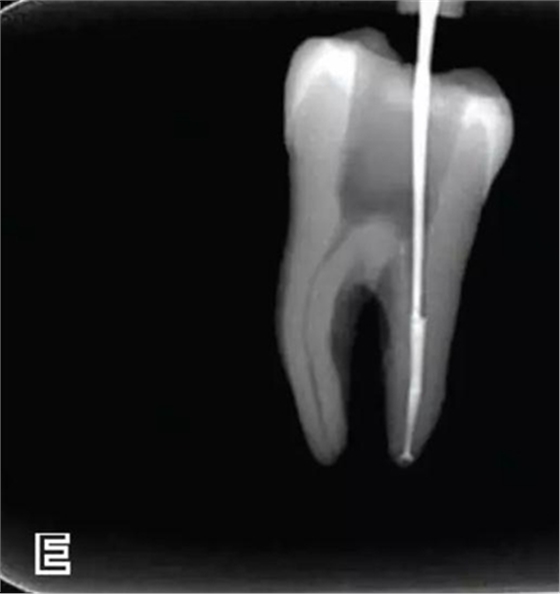

4、放置主尖及糊劑

將主尖的尖1/3 部分蘸一薄層根充糊劑,緩慢插入根管內(nèi),并左右旋轉(zhuǎn)主尖,以將根充糊劑均勻涂布于根管壁上,如圖4所示。

圖4 放置主尖及糊劑,A.放置主尖及糊劑 B.X線片下示主尖及糊劑的放置